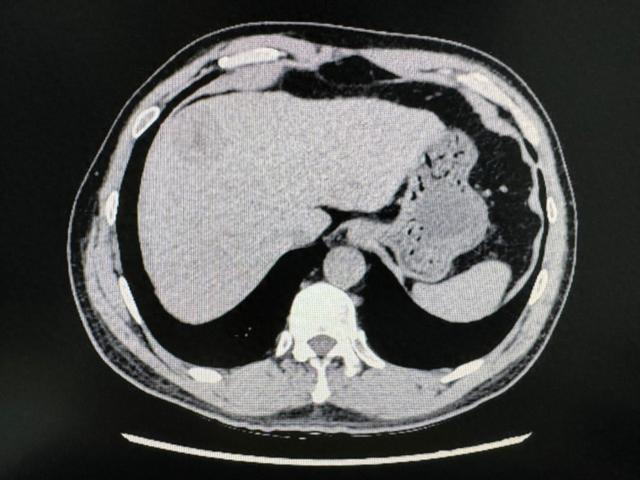

在住院期间,患者查上腹部CT后提示肝左右叶交界处肝癌,经同济医院肝胆外科中心主任谭蔚锋会诊后进行后续治疗。

术前影像学资料

1月4日行腹腔镜下特殊肝段切除术(肝中叶IVA+VIII段),术中病理为肝细胞癌。